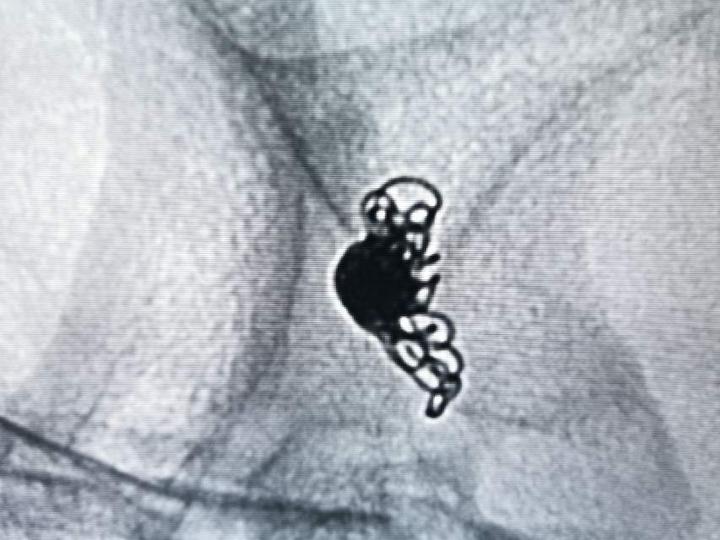

破裂的宽颈不规则前交通动脉瘤,仍然坚持急性期单纯致密栓塞。